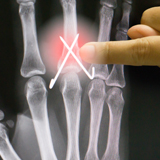

A central slip injury can be due to either a fracture at the base of the middle bone (avulsion) or from a tear in the fibres of the central slip itself (tendinous). You may need an x-ray to check if the bone is broken as well as the tendon being damaged. The therapists at Action Rehab Hand Therapy Clinic can organise an Xray referral for you. They will also assess your finger movement, swelling and pain in order to confirm the diagnosis.